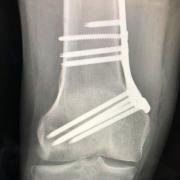

Distal femoral osteotomy is usually of the closing wedge variety, where a wedge of bone is removed and the space closed and held in place with screws until the bone unites across the gap. The 'hardware' is generally eventually removed once the bone is fully reunited.